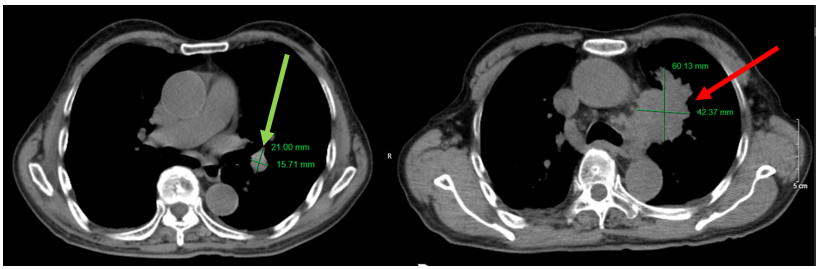

Hình 6. Hình ảnh khối u phổi trái với kích thước 21×16 mm (đang điều trị, mũi tên xanh), tăng kích thước lên 60×42 mm (sau khi bỏ điều trị 3 tháng, mũi tên đỏ) trên phim chụp cắt lớp vi tính lồng ngực, cửa sổ trung thất.

Hình 7. Hình ảnh khối u phổi trái với kích thước 21×16 mm (đang điều trị, mũi tên xanh), tăng kích thước lên 60×42 mm (sau khi bỏ điều trị 3 tháng, mũi tên đỏ) trên phim chụp cắt lớp vi tính lồng ngực, cửa sổ nhu mô.